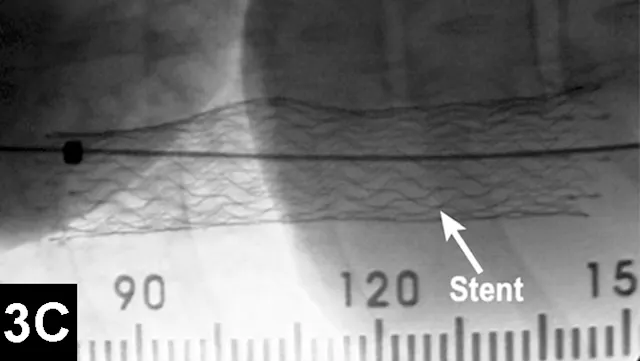

Tracheal collapse is characterized by clinical signs such as cough, raspy breathing, and dyspnea. Signs can often be treated palliatively with cough suppressants, bronchodilators, sedatives, tranquilizers, or NSAIDs, yet adequate control of disease is not always possible. Candidates for surgery include patients in which initial conservative medical management has failed. However, excessive morbidity and mortality rates have been reported for the extraluminal ring prosthesis open surgical procedure.3

Clinical improvement can be achieved in 75% to 90% of animals treated with self-expanding metallic stents (Figure 1), an IR procedure.4 Immediate adverse events were mostly minor; however, a perioperative mortality rate of about 10% was reported. Longer-term adverse events included shortening of the stent, fracturing of the stent, progressive tracheal collapse, and excessive granulation tissue.

Figure 1A: Serial lateral fluoroscopic images of a dog with tracheal collapse.

A positive pressure ventilation demonstrates maximal dilation of the trachea. A marker catheter in the esophagus is used to account for radiographic magnification.